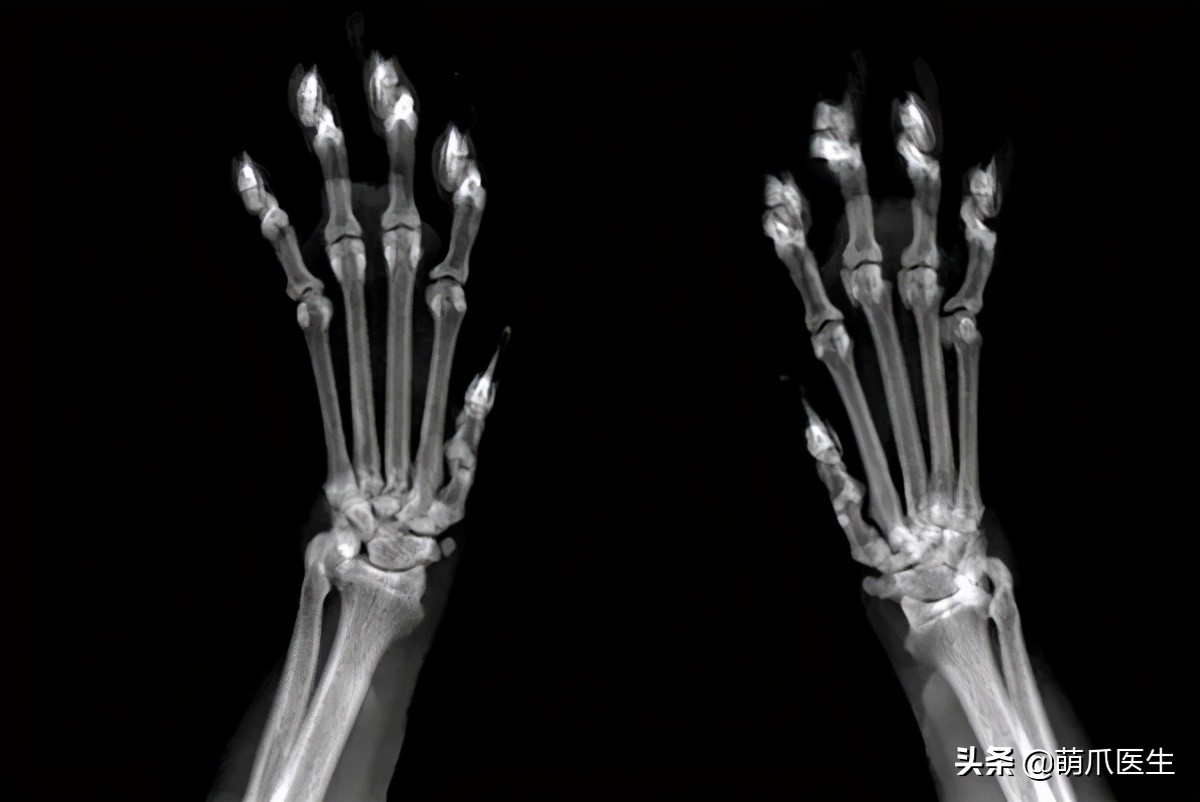

有经验的网友还贴上了自己家猫的X光,表示猫爪分明长这样啊!

但可以明确的是,猫咪骨骼发育完全时,爪爪的X光片绝对就长这样: